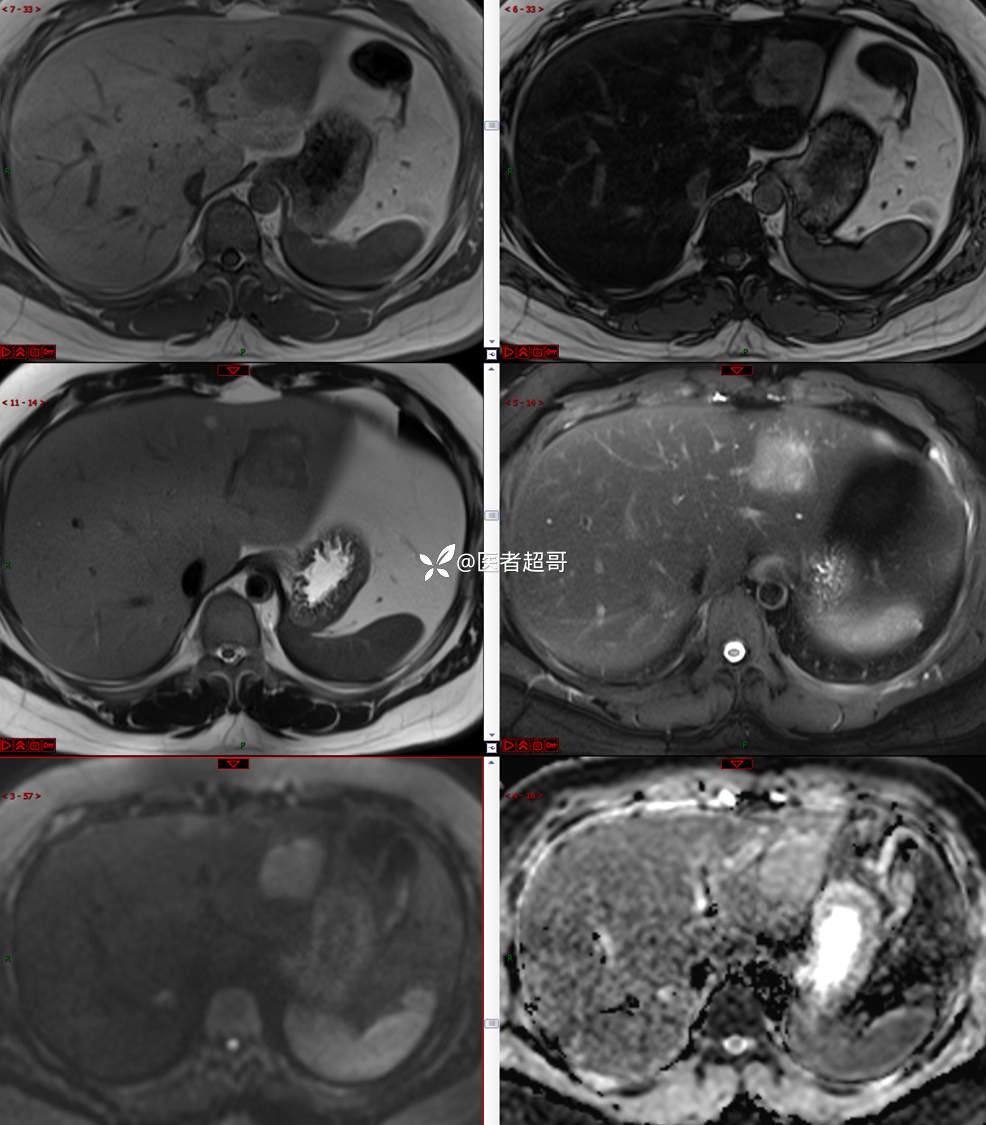

【影诊笔记800】青年男性,肝脏占位,特殊对比剂提示富血供,您能想到啥?有结果!

男,31y

主 诉:发现肝占位性病变5天。

现病史:患者缘于5天前体检时发现肝占位性病变,未予以特殊处置。现患者为求系统诊治就诊于我院,行普美显提示:肝左叶富血供占位,请结合临床及其他检查,肝多发血管瘤,脂肪肝,肝囊肿,请结合临床。门诊以“肝占位性病变”收入我科。病程中,饮食睡眠可,二便可,近期体重未见明显变化。